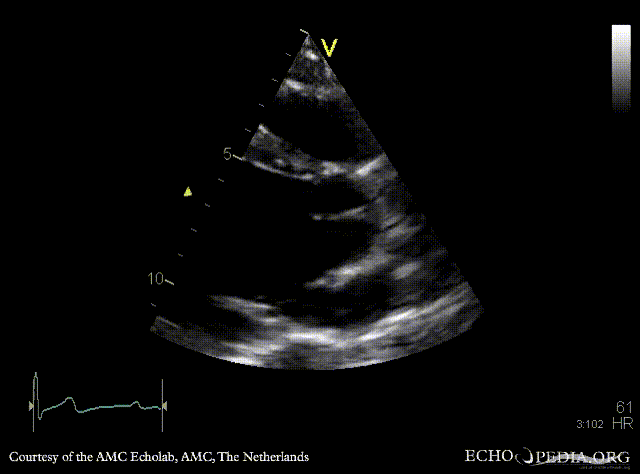

A4CH: left ventricle dilatation A3CH: Color Doppler, severe aortic regurgitation